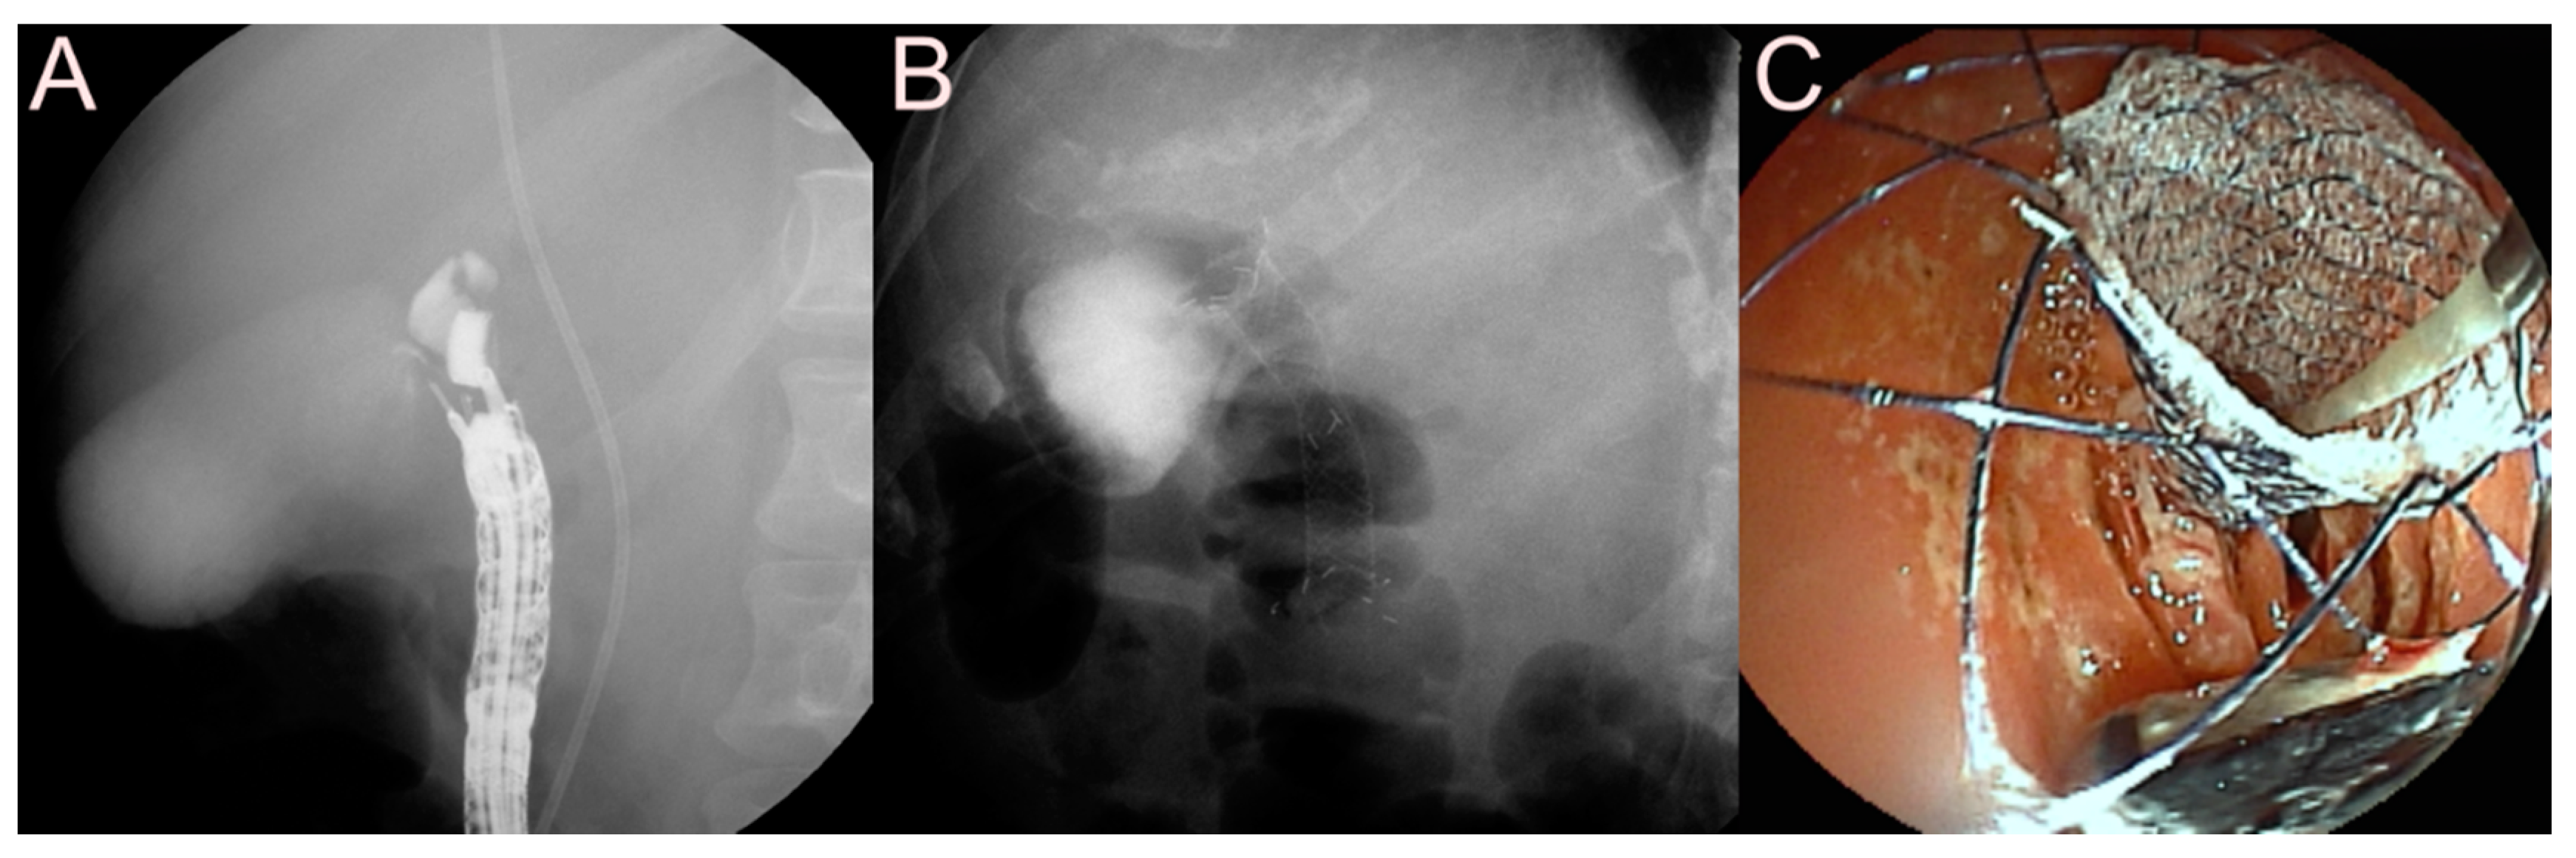

2.4.2. Use of the SEMS